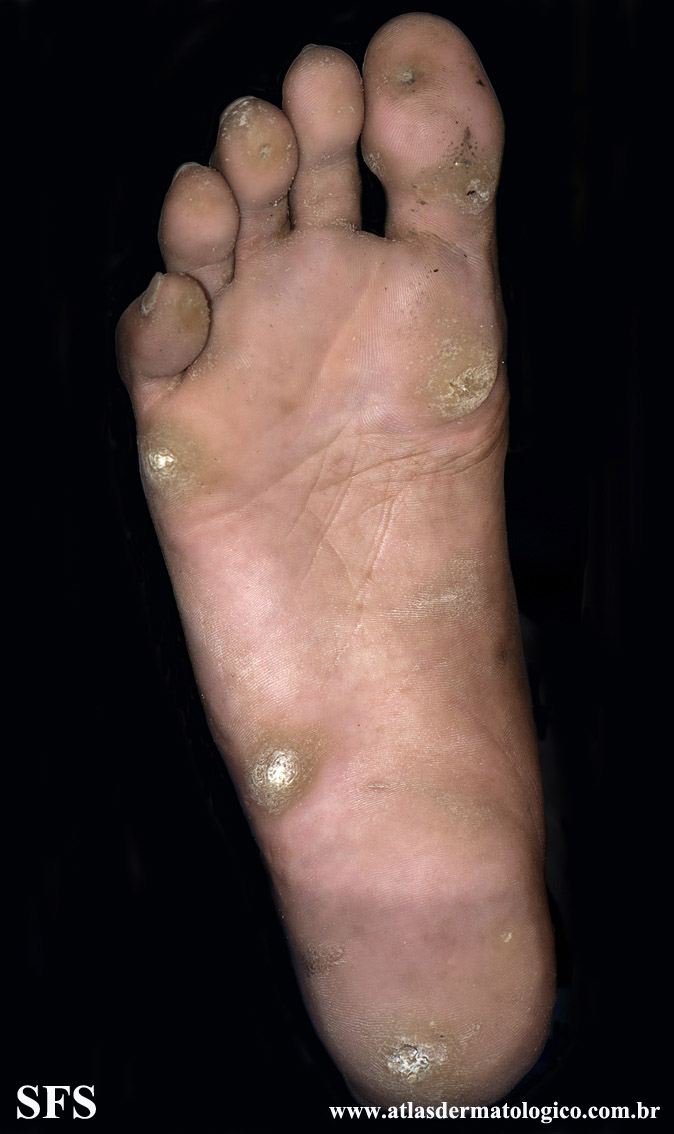

palmoplantar_keratoderma-focal_keratoderma